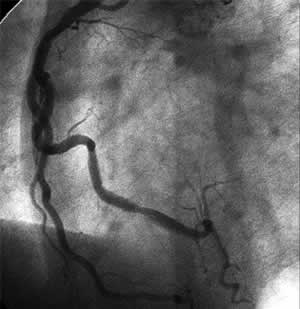

| Diagnosis: EA, DVD Present Illness: '99.2~ EA '99.12.16 Multiple stenting for #1~4AV '01.2.22 POBA for #2~3, #13 |

| Final CAG Findings:'01.9.21 LVG: asynergy (A), EF: 61% CAG: #3 75%, #9 90%, #12 75% |

![]() Cutting Balloon 3.25mm@15atm |

F-1 : 3 months follow-up angio